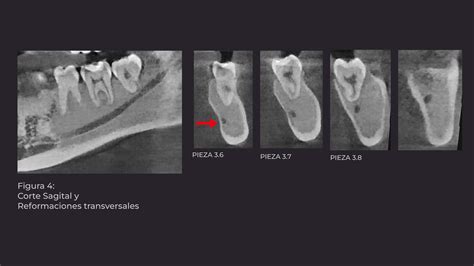

Se realizó Denta-Scan maxilar para valorar con más precisión la posición de los dientes incluidos10. Se observaron unos maxilares con aumento de densidad de forma generalizada, heterogénea, siguiendo un patrón radiológico en vidrio deslustrado. Al observar el maxilar se apreció una expansión grave de éste con ocupación parcial de los senos maxilares y retenciones dentarias múltiples con una situación muy alta y palatina de los caninos. El diagnóstico de presunción fue displasia fibrosa poliostótica (fig. 3).